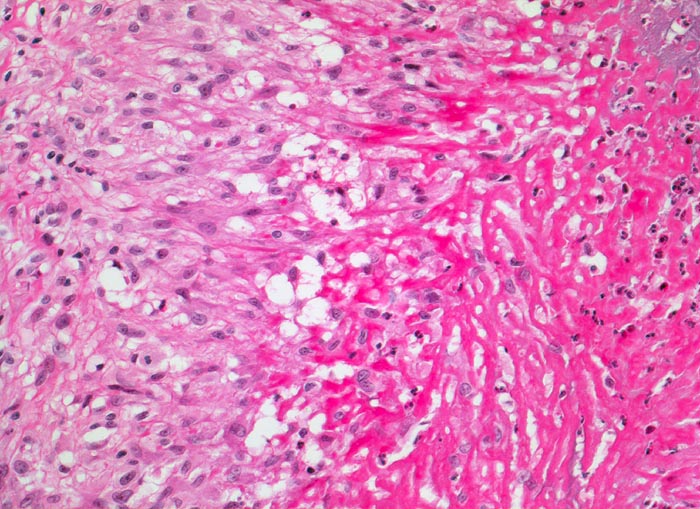

Rechts im Bild hypereosinophile fibrinoide Nekrose mit Einschluss von neutrophilen Granulozyten. Angrenzend an die fibrinoide Nekrose links im Bild palisadenförmig angeordnete Epitheloidzellen. Etwas weiter aussen sind locker eingestreute Lymphozyten und Granulozyten zwischen den Epitheloidzellen erkennbar.

Patientin mit rheumatoider Arthritis. Derber, verschieblicher subkutaner Knoten an der Streckseite des Unterarmes nahe des Ellenbogens.